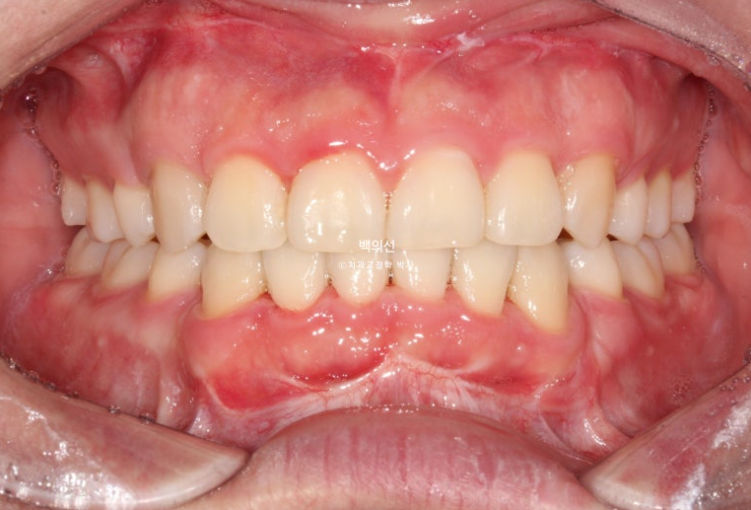

25년 4월부터 8월까지 5개월간 14개 장치를 모두 낀 후 모습입니다.

25.08

남아있던 공간은 추가장치로 깔끔히 없어졌습니다.

치근흡수는 없으며 치근평행도는 좋습니다.

총 치료기간은 10개월, 재제작 1회 입니다.

앞니가 깊게 물리는 과개교합도 좋아졌습니다.